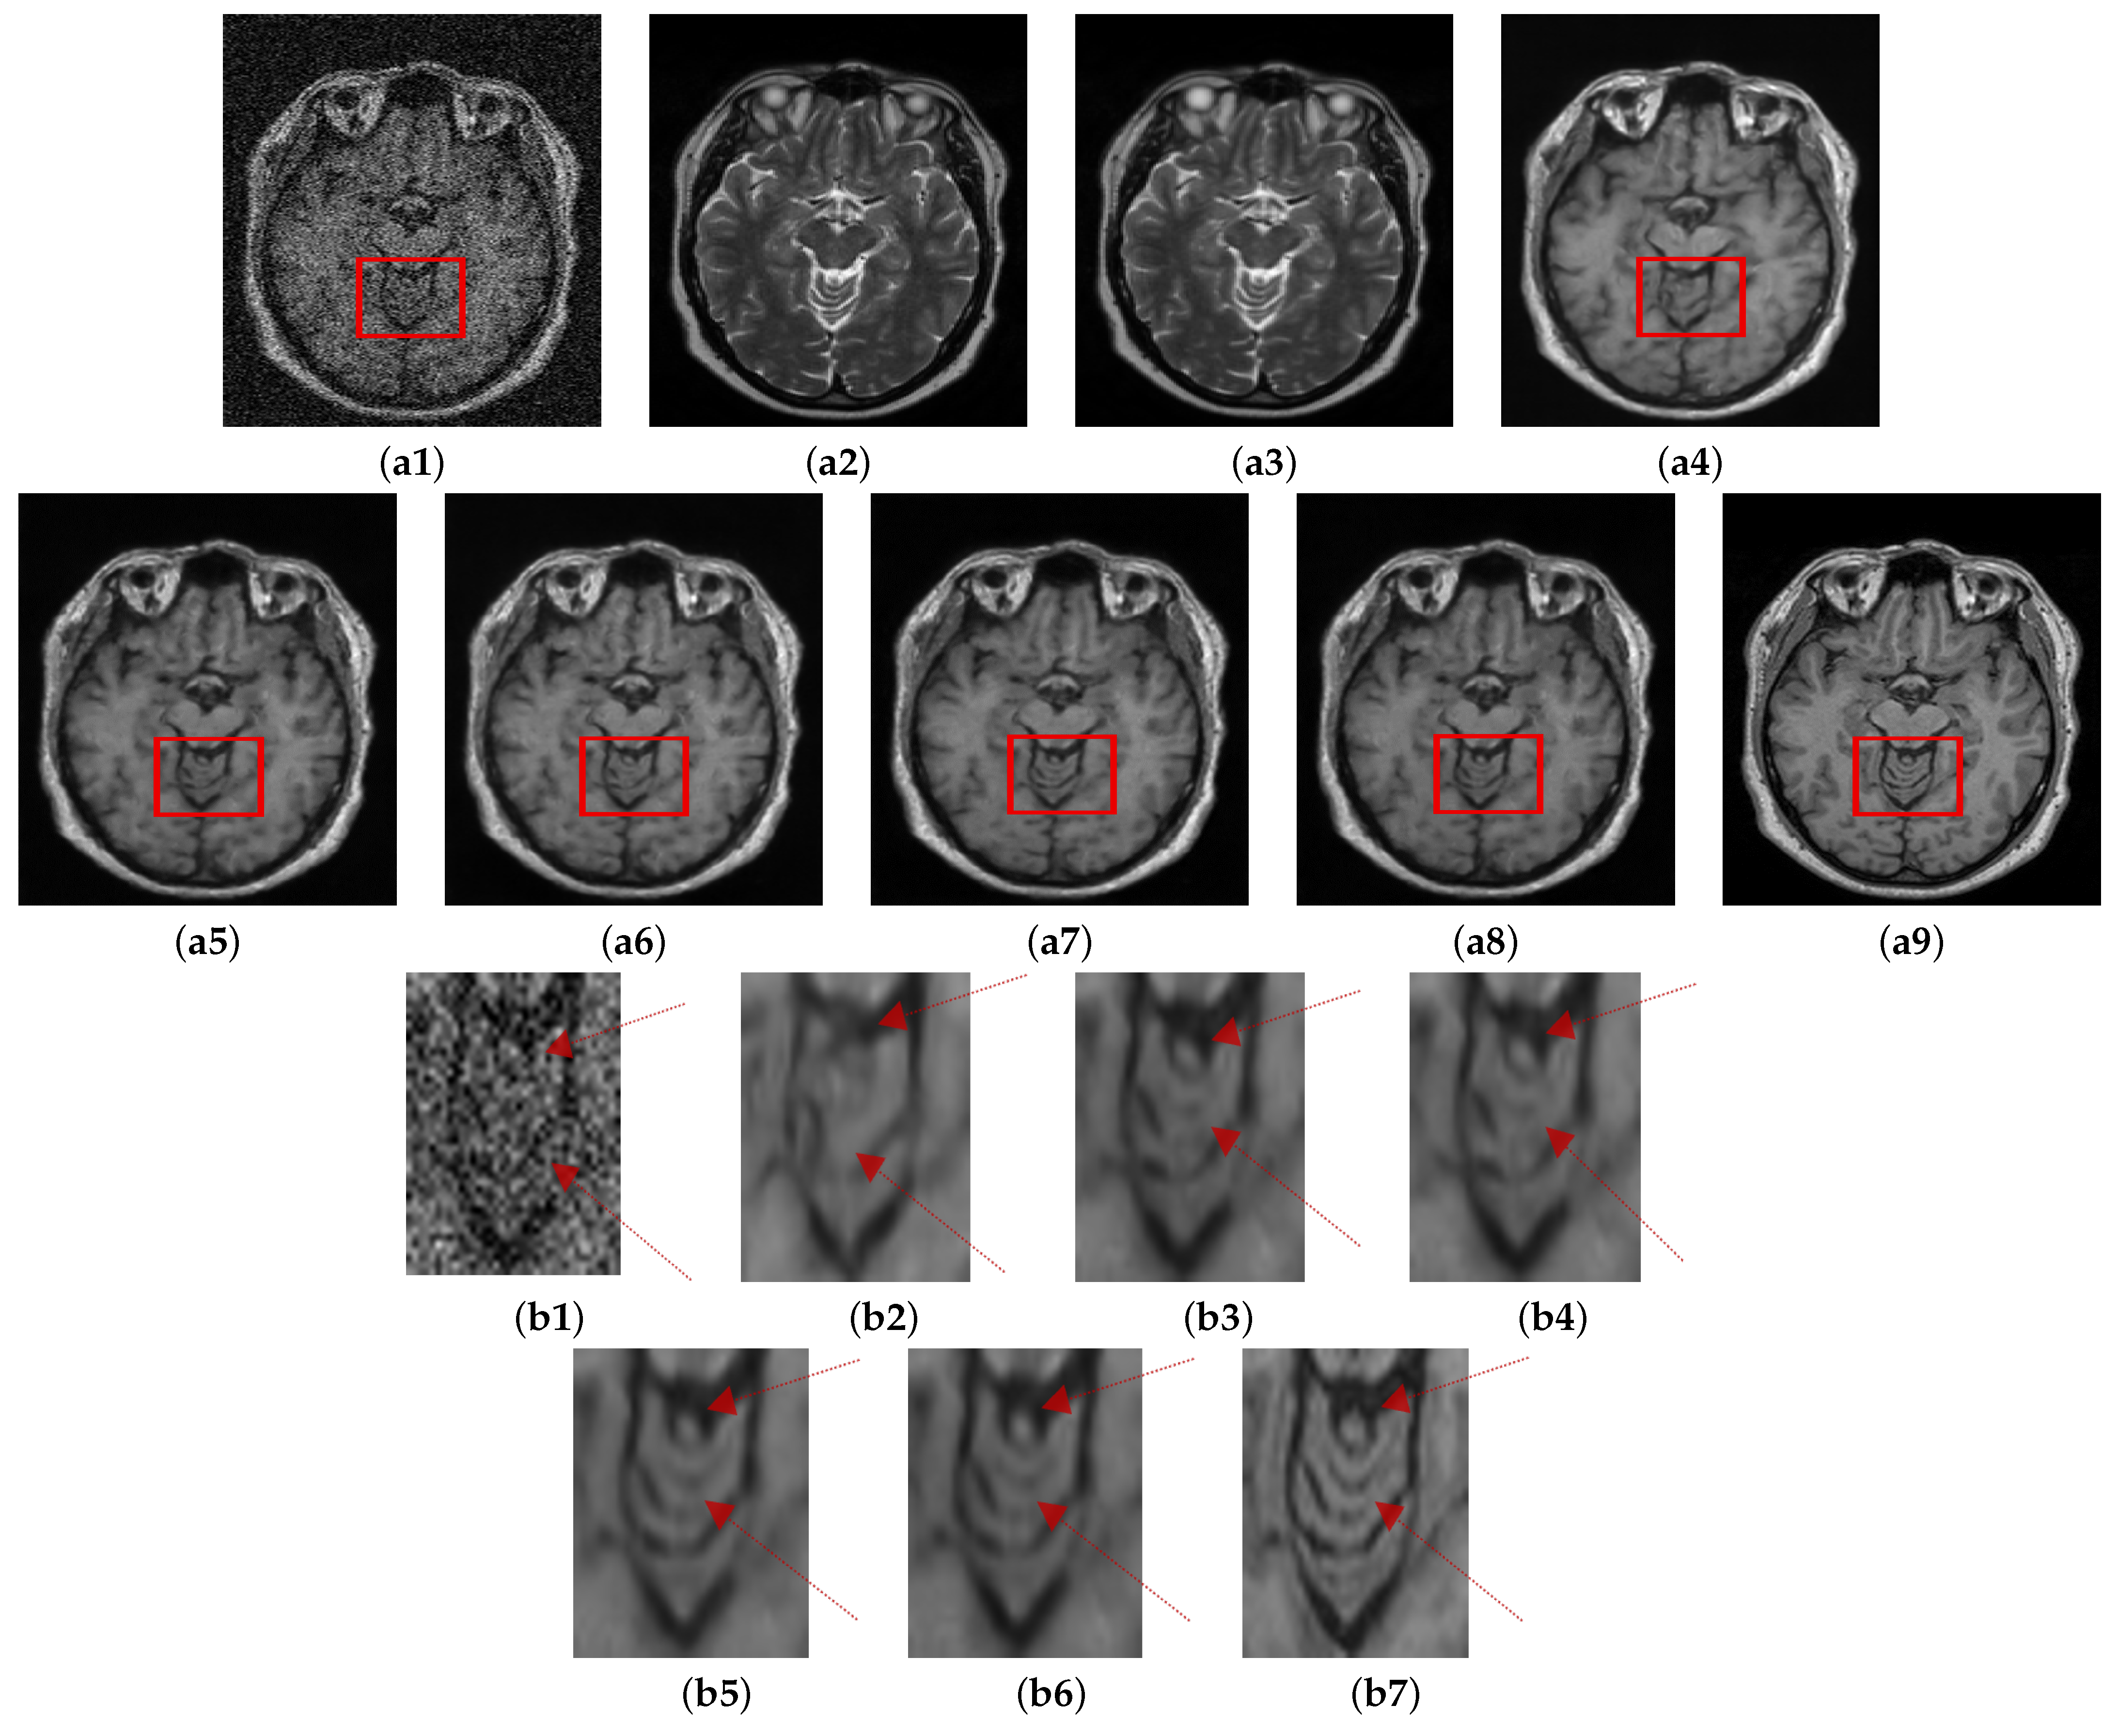

The visual comparison of the performance of the proposed method with other denoising methods conducted on the Guys dataset (13% noise) is shown in Figure 7. NLM and SURE exhibit worse performance among all the methods tested. NLM eradicates significant details from the image while SURE removes minimal noise. BM3D performs slightly better than the two approaches. MCDN preserves structural information of the image; however, it leaves some noticeable noise in the image. The performance of FFD-Net visually in this case is comparable with C M G D N e t . The quantitative assessment also validates the visual observations, which are shown in Table 3. For instance, NLM and SURE are ranked low at all the noise levels by PSNR and SSIM. BM3D performs better than both NLM and SURE. It is pertinent to mention that even the more robust conventional denoising methods such as BM3D leveraging the benefits of spatial and transform domains rely on pre-defined assumptions that do not work well under several types and levels of noise. On the other hand, deep learning approaches allow the underlying model to learn various levels of feature representations from raw to the higher level. In the context of denoising, the model thus learns the uncertain noise distributions from the input data. Consequently, these techniques can adapt to several types of noise efficiently. The deep learning methods in the proposed study perform better than the conventional methods on all the metrics. However, the cross-modal image information further enhances the network learning capability. Overall, the images denoised using all the methods still look blurry compared to the ground truth. It is because it is not possible to recover the image contents completely that have been corrupted by noise without any loss of information. However, it can be sensed that the denoising at level 8% introduces less blur compared to the denoising applied to images containing 13% noise. Overall, the proposed method achieves the best performance among all the methods both in PSNR and SSIM. C M G D N e t exhibits an average gain of 4.7% in SSIM value compared to the second-best MCDN (0.89 against 0.85).

Figure 7. Comparison of proposed method with state of the art denoising methods. (a1) Noisy. (a2) NLM [10]. (a3) SURE [58]. (a4) BM3D [59]. (a5) MCDN [24]. (a6) FFD-Net. (a7) C M G D N e t s g . (a8) GT.